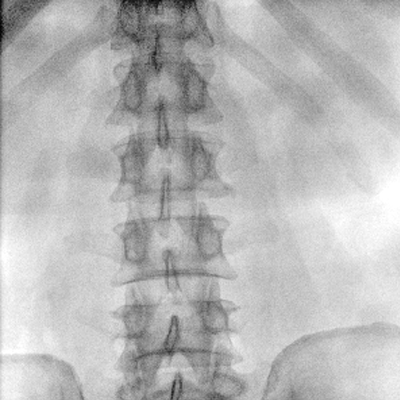

大尺寸動(dòng)態(tài)平板探測器,高DQE、低噪聲、圖像清晰。采用多分辨率圖像增強處理技術(shù),不同部位不同圖像處理算法,滿(mǎn)足客戶(hù)多樣化的需求。

采用智能變頻脈沖透視技術(shù),優(yōu)化圖像質(zhì)量的同時(shí)降低輻射劑量,呵護醫患健康

多角度自由旋轉,滿(mǎn)足患者復雜擺位需求。